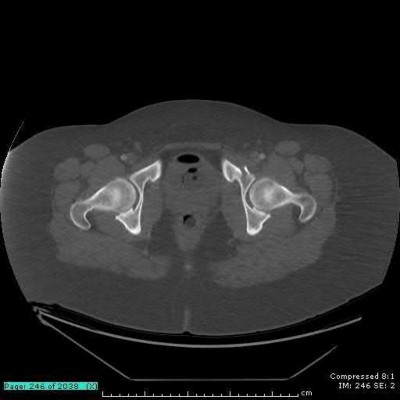

A 35 year-old female presents after prolonged extrication from a motor vehicle collision complaining of severe pelvic pain. Physical examination reveals diminished perianal sensation. She is otherwise neurologically intact. Figures A through D are radiographs and representative CT cuts of her injury. Which of the following nerve roots has likely been injured by the acute trauma?

The clinical scenario is consistent with a high-energy sacral fracture. The radiographs in figures A and B demonstrate a sacral fracture with posterior displacement of the right hemipelvis seen on the inlet view. Figures C and D are axial and sagittal CT images which show a displaced fracture of the right

hemisacrum along with a transvere fracture component through the S3 body . Diminished perianal sensation is concerning for an S2 nerve root injury.

Mehta et al reviewed the current management of sacral fractures. They note that the S1 and S2 nerve roots are more likely to be injured with sacral fractures as they occupy 1/3 to 1/4 of the neural foramina, as opposed to S3 and S4, which only occupy 1/6 of the neural foramina.

Robles reviewed the current literature to ascertain principles of evaluation and treatment for transverse sacral fractures. The author notes that injury to nerve roots S2 to S5 is manifested by impairment of urinary and anal continence and sexual function.